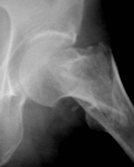

Die Fraktur ist schlecht reponiert und der Schenkelhals

verdreht, der Winkel des Nagels ist zu steil